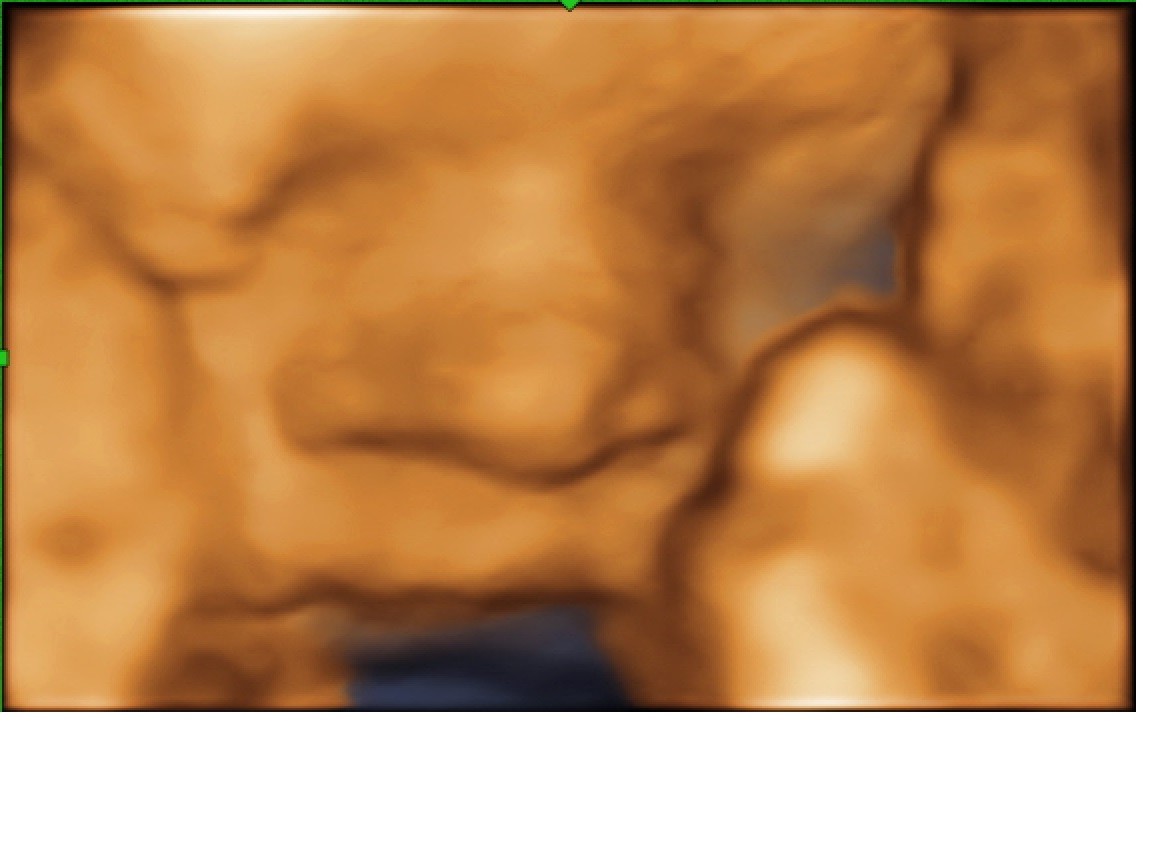

Ja już po usg. Lilka pozostaje Lilką

waży już 1350g. Ma nogi długie na 29 tyg, brzuszek na 28 tyg a inne wymiary na 27tyg czyli szczupła i wysoka po mamie

Taką ma buzię cudną